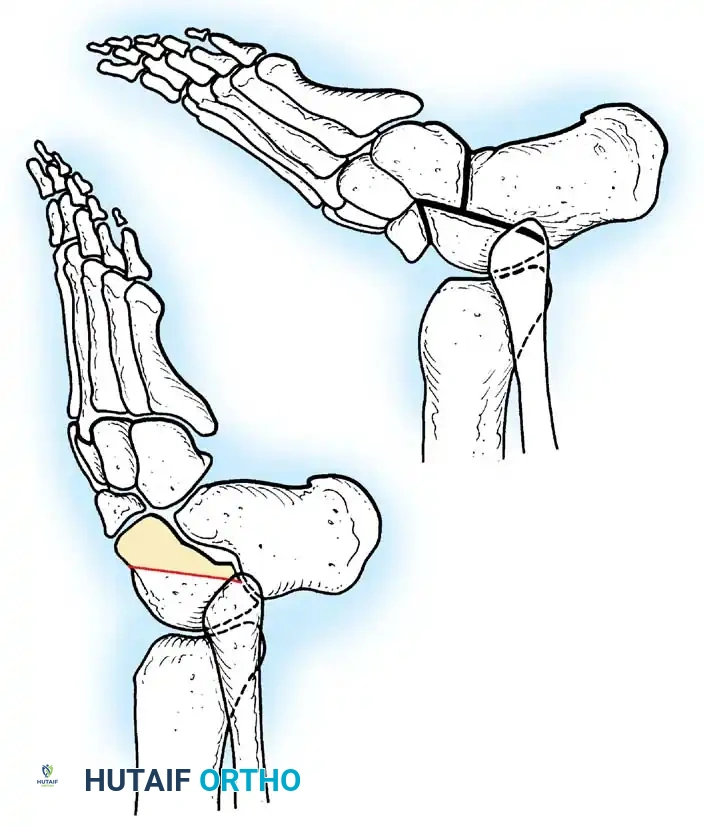

Paralytic Calcaneus:

A devastating deformity resulting from triceps surae paralysis. The unopposed dorsiflexors pull the foot into calcaneus, while the intrinsic muscles and plantar fascia contract, creating a calcaneocavus deformity. Reconstruction requires plantar fascia release, followed by transfer of the tibialis posterior, peroneus longus, and flexor hallucis longus to the os calcis to restore plantarflexion power.

Image